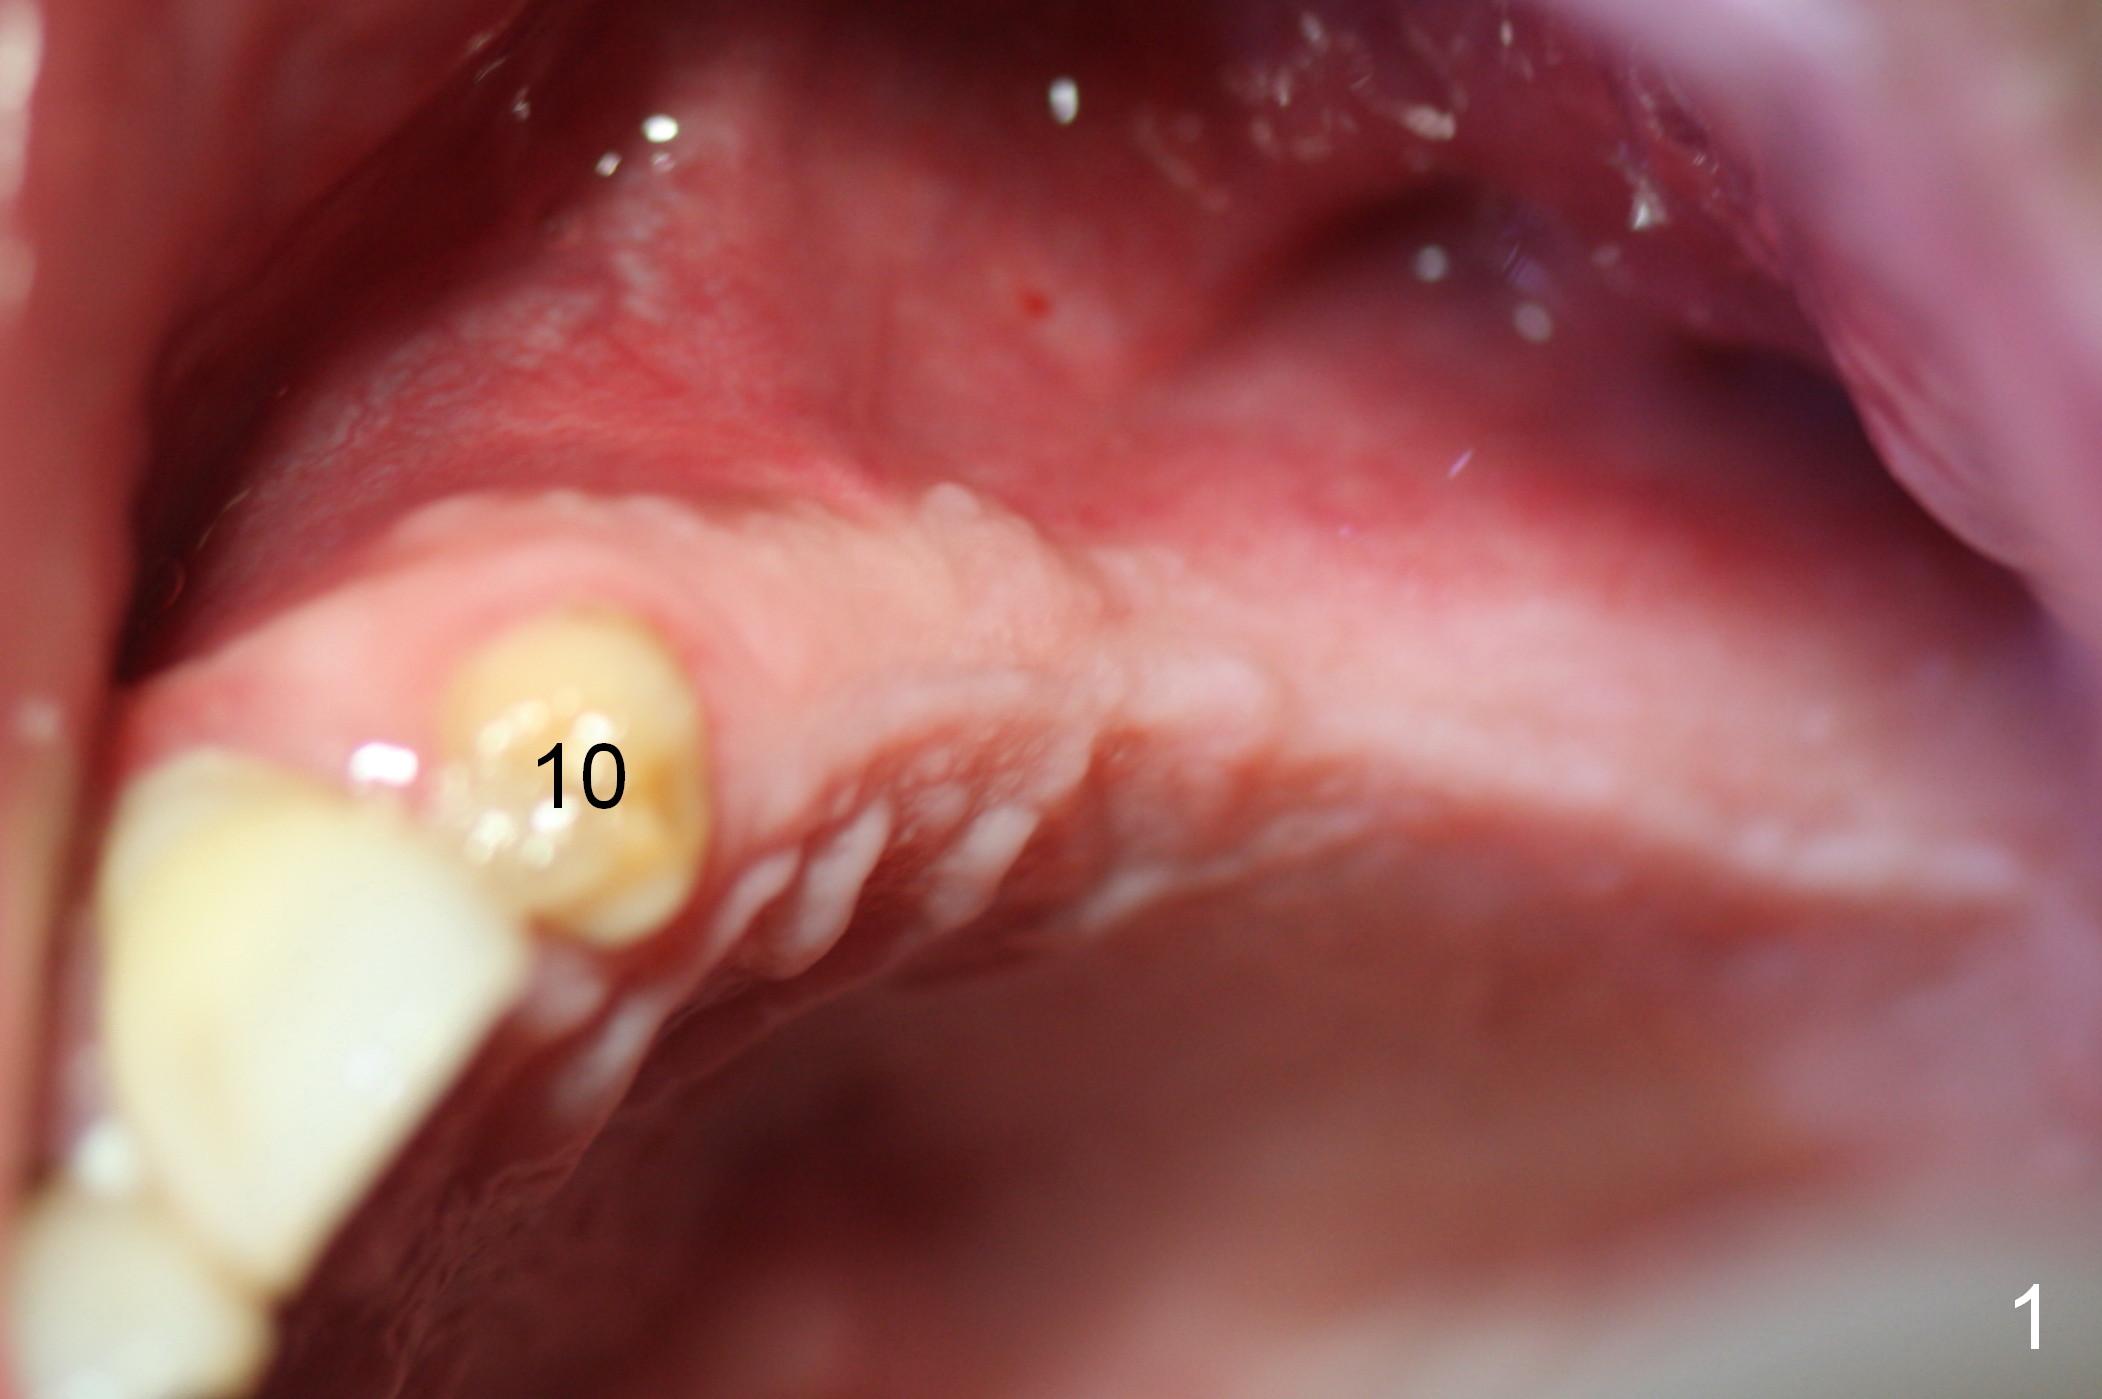

When the patient returns for implant placement (2nd visit after initial exam), he reveals that he is a dental phobic. He requests placement of 4 implants in the upper left quadrant, instead of 2. Narrow ridge is unexpected in the canine and premolar area (Fig.1). Limited bone height at #13 (Fig.3 arrowheads: sinus floor) is found when initial drills are in place (Fig.2,3). A 2-piece implant (4.5x17 mm tissue-level) is placed at #10 after extraction, while 1-piece implants are placed at 11 (3x17 mm (tissue-level, 15 °) and 12 and 13 (bone-level, 2.5x14, 12 mm, respectively; Fig.4,5). In fact the 1 piece implant at #13 is not completely placed (Fig.5). It is removed, the apical 3 threads are cut off (Fig.6 <, since a shorter implant was unavailable in the office) and the remaining implant is re-inserted. The insertion torques of the 4 implants are ~ 60, ~ 35, < 35 and 15 Ncm, respectively. After adjustment (Fig.7), immediate provisionals are fabricated at #10 and 11 (Fig.8, later splinted with composite), while perio dressing is applied around the implants at #12 and 13 and the provisionals at #10 and 11. There is no nasal hemorrhage postop. Although the perio dressing is loose 1 week postop (Fig.9), it is not removed. When the upper lip fissure (Fig.9 <) heals, provisionals at #12 and 13 are planned to be splinted to the other two ones. Two weeks postop, the upper lip fissure heals, the perio dressing dislodges and the implants at #12 and 13 are stable (Fig.10). After abutment height adjustment, a splinted provisional is fabricated over these 2.5 mm 1-piece implants (Fig.11).